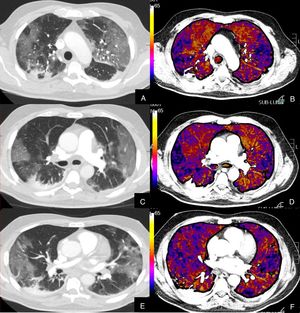

Paciente que, a pesar de buena evolución de su enfermedad por infección COVID-19, presenta elevación del D-dímero.

Imágenes axiales de una angiografía pulmonar con TC y mapa de yodo, en ventana de parénquima (A, C, E) a nivel de lóbulos superiores, medios e inferiores y sus correspondientes imágenes del mapa de yodo (B, D, F).

Paciente con afectación moderada por COVID-19, con consolidaciones subpleurales de predominio en segmentos posteriores y basales, sin TEP en arterias pulmonares principales ni periféricas ni defectos de perfusión en el mapa de yodo (colores amarillos, naranjas).